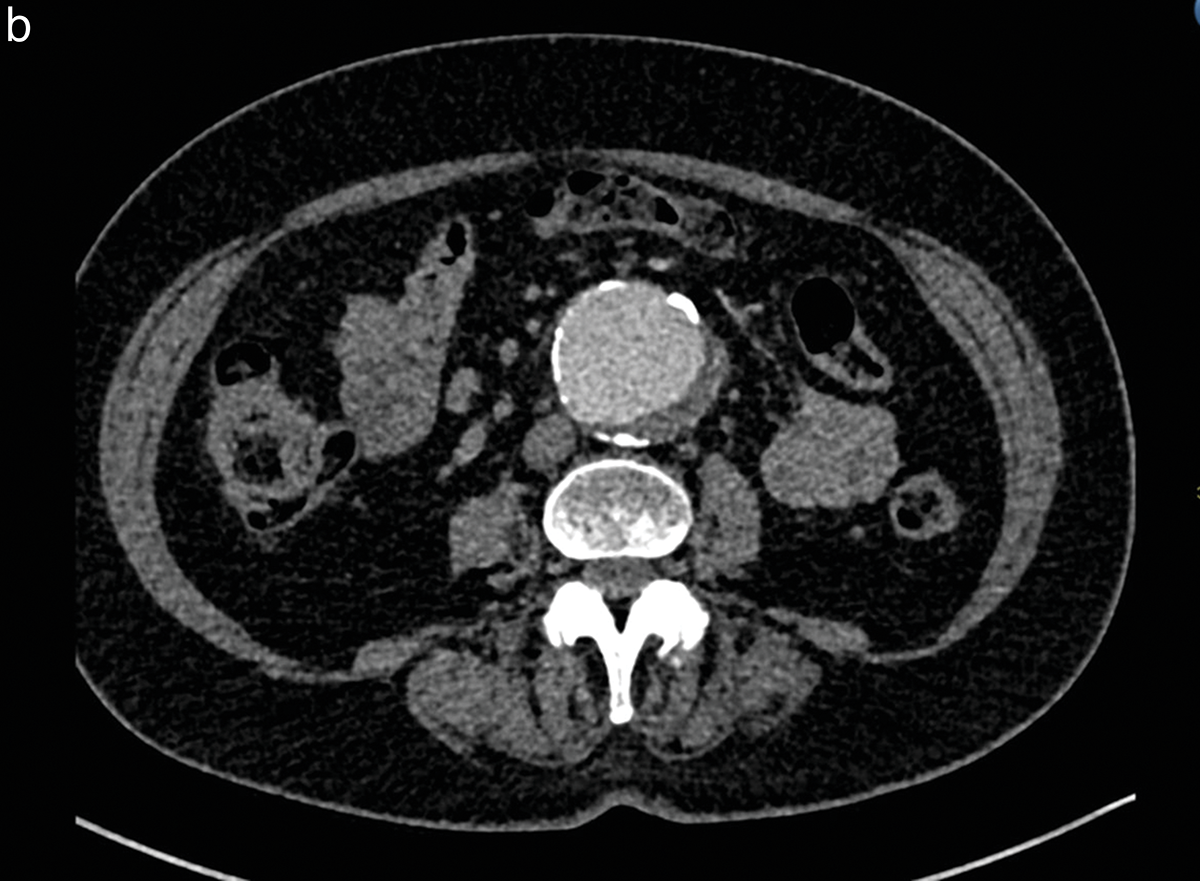

Figure 2 (a, b)

Patient with an abdominal aortic aneurysm, included in study Group 2.

After intravenous injection of 15 cc of iodinated contrast medium, the qualitative imaging score was 2 by the two independent observers for the axial slice at the renal artery level (a) and was 3 at the infrarenal level (b).